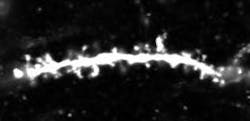

Loss of long-term memory for specific learned experiences is a hallmark of early Alzheimer's disease that is also exhibited by mice genetically engineered to develop Alzheimer's-like symptoms. Building on their previous work that identified and activated memory cells, a group led by RIKEN Brain Science Institute and RIKEN-MIT Center Director Susumu Tonegawa has now shown that spines—small knobs on brain-cell dendrites through which synaptic connections are formed—are essential for memory retrieval in these mice with Alzheimer's. Fiber-optic light stimulation can re-grow lost spines and help mice remember a previous experience.

Memories restored with this method faded away within a day, and the researchers next sought to understand why this happens. They noted a reduction in the number of spines as the mice aged and their Alzheimer's progressed. Their waning memory for the fear training was also linked to a loss of these spines. Previous work had shown that spines grow when neurons undergo long-term potentiation, a persistent strengthening of synaptic connectivity that happens naturally in the brain, but can also be artificially induced through stimulation.

Through repeated stimulation with high-frequency bursts of light to the hippocampal memory circuit in Alzheimer's mice, the team was able to boost the number of spines to levels indistinguishable from those in control mice. The freezing behavior in the trained task also returned and remained for up to six days. The implication is that restoring lost spines in the hippocampal circuit facilitated retrieval of the specific fear experience and its associated freezing behavior.